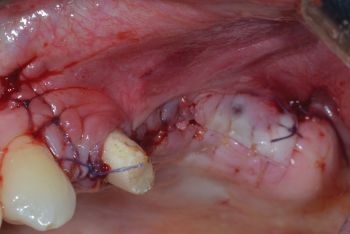

Finally, the access flap was sutured using both resorbable monofilament and multifilament materials (Fig. 15).

Fig. 15: Suturing the access flap with absorbable monofilament and multifilament sutures